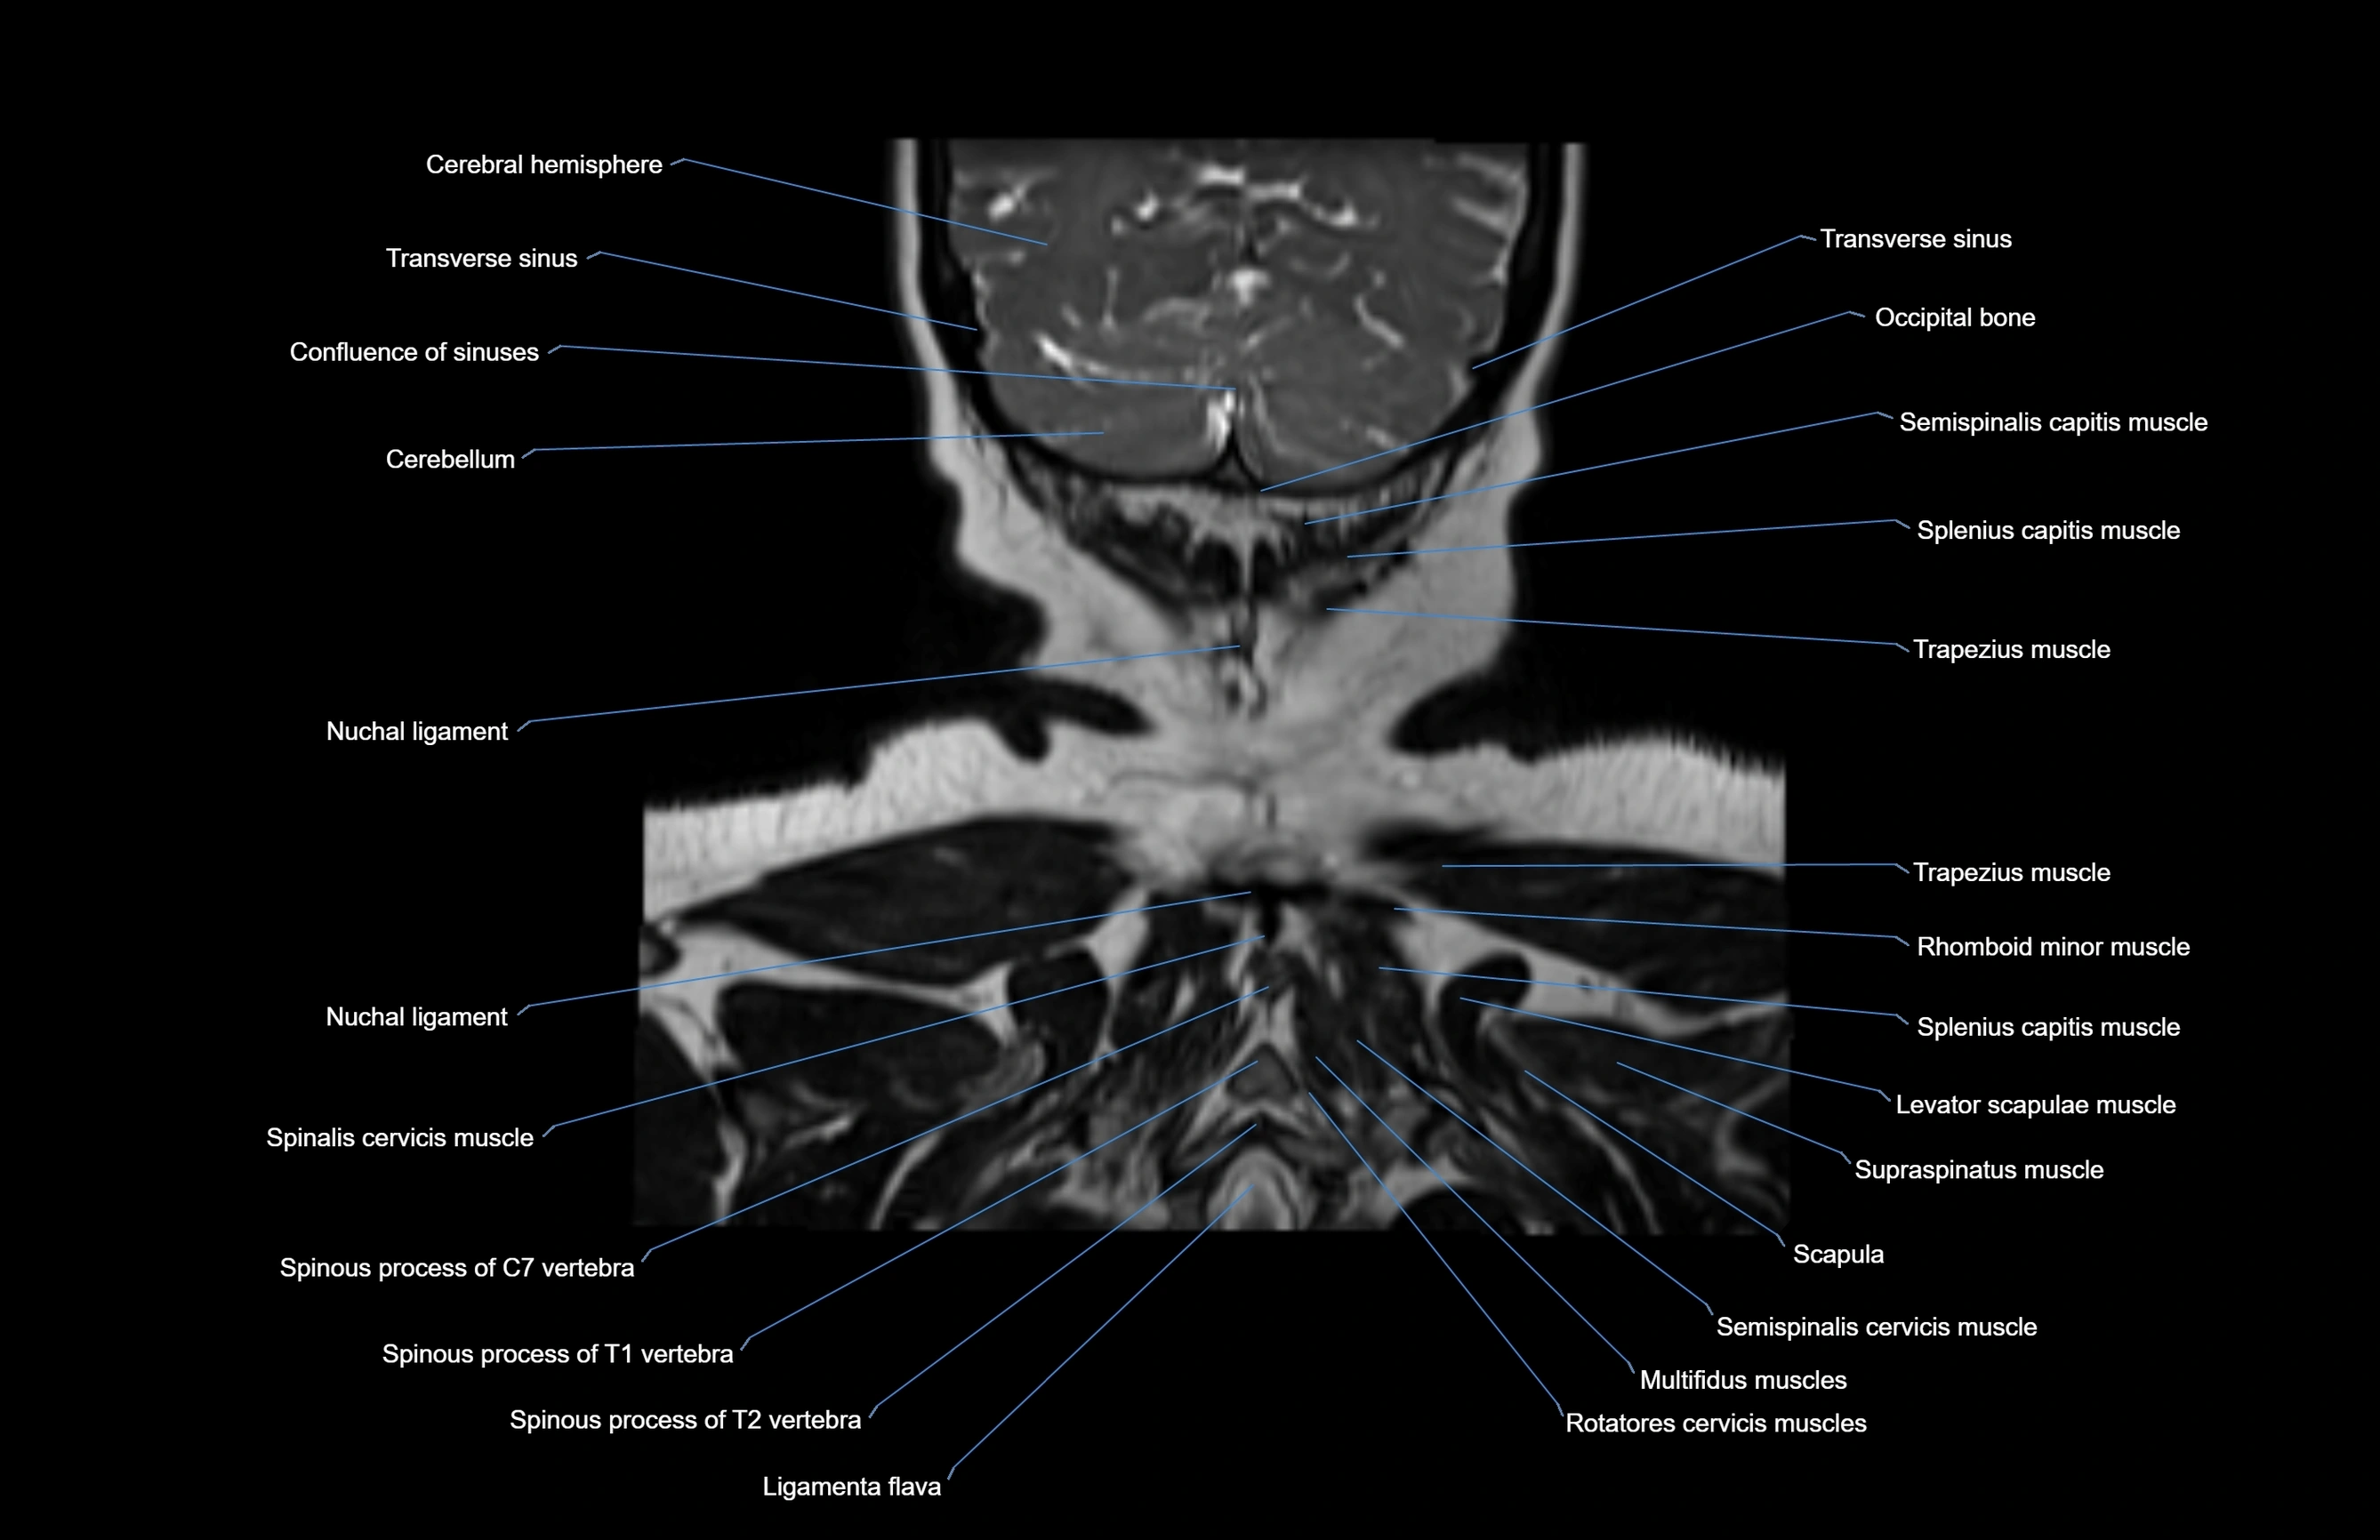

- Nuchal ligament

- Multifidus muscles

- Rotatores cervicis muscles

- Spinalis cervicis muscle

- Semispinalis cervicis muscle

- Supraspinatus muscle

- Scapula

- Trapezius muscle

- Splenius capitis muscle

- Ligamenta flava (Ligamentum flavum)